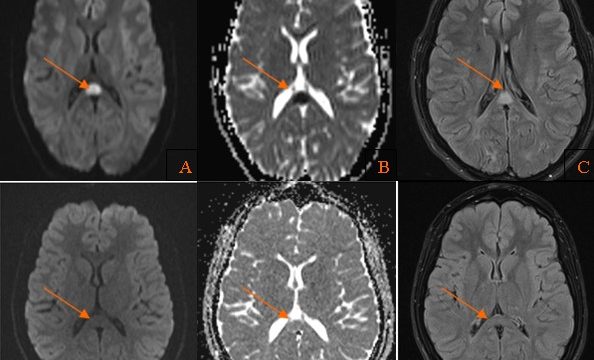

Historia Clínica

Varón de 40 años con esclerosis múltiple remitente-recurrente ya conocida, que consulta por disartria de varios días de evolución.